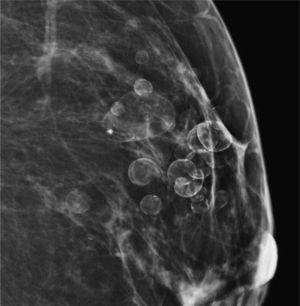

Calcificaciones intraquísticas (fig. 5). Son calcificaciones dentro de quistes. Tienen como característica principal que presentan un aspecto diferente en las distintas proyecciones: son amorfas en la proyección cráneo-caudal y curvilíneas (en forma de taza) en la proyección lateral (90°)3.